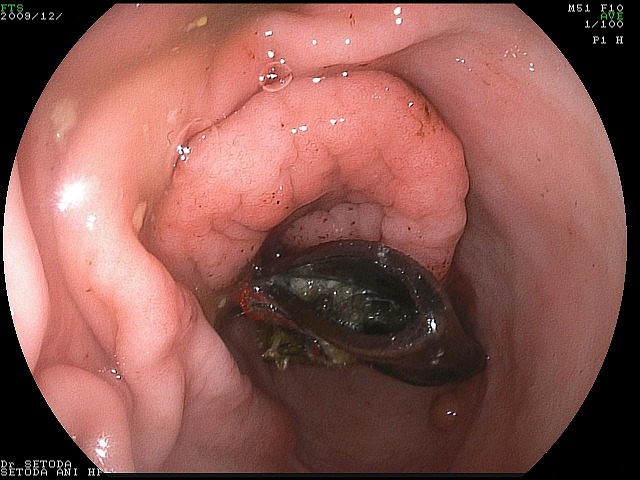

「ぬいぐるみを作っていたのですが、この時に使っていた針を飲み込んだかもしれません!」と言う事であるワンちゃんがいらっしゃいました。すぐにレントゲンを撮っておなかの中を調べてみると・・・

Img6576.jpg

Img6577.jpg

胃の中の針はすぐに見つけ出すことが出来ましたが、他にも何か胃の中にあるようです。